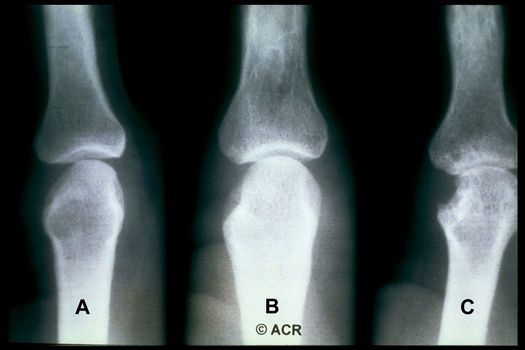

Read ArticleAI Identifies and Predicts Radiographic Change in Rheumatoid Arthritis

The American College of Rheumatology's (ACR) has published a preview of new research from ACR Convergence 2023 showing that AI and a deep learning system could accurately identify and predict joint space narrowing and erosions in hand radiographs of patients with rheumatoid arthritis (RA).

Read ArticleX-Rays Questioned for Diagnosing Early Rheumatoid Arthritis

Routine hand and foot radiographs in more than 700 patients being evaluated for rheumatoid arthritis (RA) made almost no difference in diagnosing the condition nor in predicting its course, Dutch researchers said.